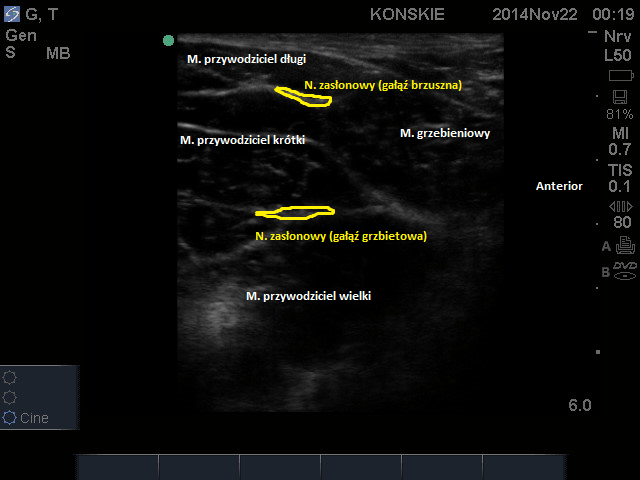

W celu lokalizacji nerwu zasłonowego liniową głowicę USG przykładamy w okolicy więzadła pachwinowego, tak aby uwidocznić naczynia udowe. Następnie kierujemy głowicę nieco przyśrodkowo i doogonowo (ok. 1-3 cm doogonowo w stosunku do więzadła pachwinowego) tak aby uwidocznić przedział mięśni przywodzicieli. Najbardziej przyśrodkowo odnajdujemy mięsień grzebieniowy, bocznie w stosunku do niego grupę trzech mięśni przywodzicieli, idąć od góry: przywodziciel długi, krótki i wielki. Gałąź przednią nerwu odnajdziemy w przestrzeni powięziowj pomiędzy mięśniem grzebieniowym a przywodzicielem krótkim, gałąź tylną pomiędzy przywodzicielem krótkim i wielkim, w obrazie USG mają one najczęściej hiperechogeniczny wrzecionowaty kształt.